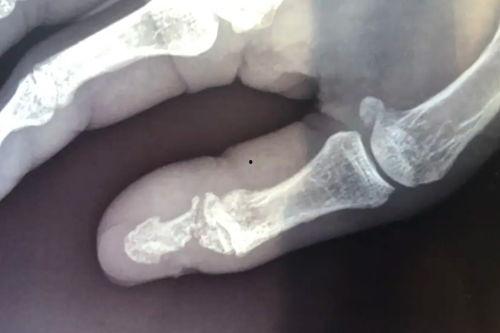

首先,让我们来看看手骨折的初期形态。骨折后的手,就像被大自然开了一个玩笑,原本整齐的骨骼变得歪歪扭扭,让人看了不禁心疼。有的骨折部位明显,骨头错位,甚至可以看到明显的裂缝;有的则较为隐蔽,需要仔细观察才能发现。这些手骨折的图片,让人不禁为受伤者的痛苦而感到惋惜。

2. 手术矫正:对于一些复杂的骨折,手术矫正是必不可少的。手术过程中,医生会小心翼翼地调整骨折部位,使其恢复到正常状态。手术后的手,会留下明显的疤痕,但这也是治愈的证明。